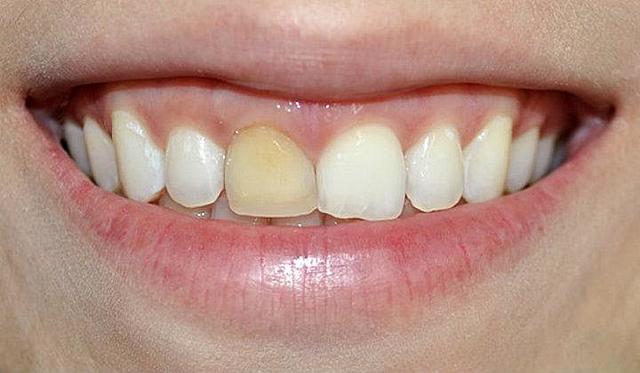

Se realizó la toma de modelos como protocolo para una correcta valoración y estudio del paciente; como también la toma de fotografías de estudio intraorales del maxilar y mandíbula. En estas fotografías intraorales se encontró que el paciente tiene el frenillo labial superior extendido. Lo que ha provocado el diastema en el paciente.

• Frenilectomía del frenillo labial superior

Frenilectomía del frenillo labial superior

Se realizará esta cirugía pre-protésica para poder tener un frente estético con las carillas directas que se colocaran posteriormente, está cirugía también ayudará que el frenillo labial no quede presionado con las restauraciones.